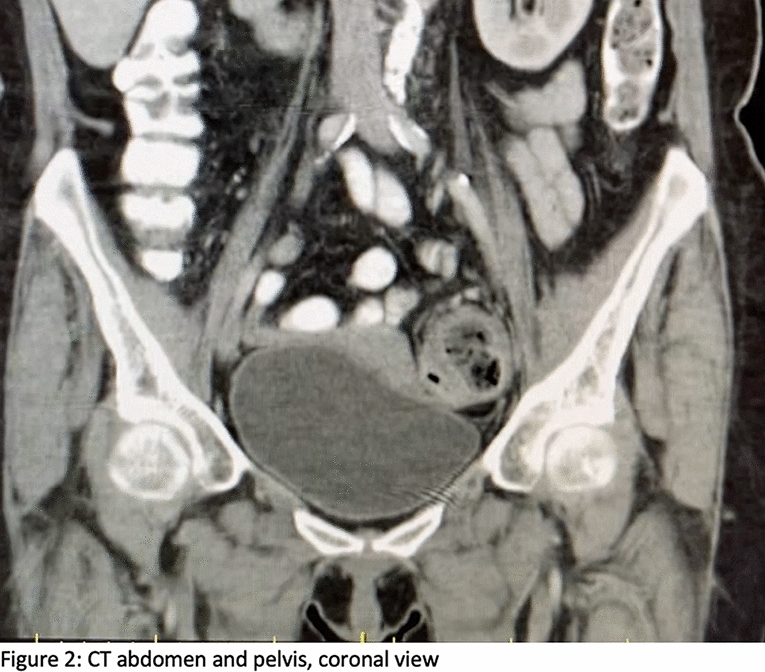

Case Presentation: We report a case of an 81-year-old male who presented to emergency department with incarcerated right inguinal hernia with small bowel contents. During his surgery, he was found to have the urinary bladder adhered to the hernia sac. The hernia sac and the urinary bladder were reduced without any complications. The patient underwent a Lichtenstein tension-free hernia repair.

Conclusion: Inguino scrotal hernia containing bowel contents is not uncommon; however, the presence of the urinary bladder is rare. It should be anticipated intraoperatively, particularly in patients with long-standing hernias. Management is surgical and Lichtenstein repair is a viable option with low rates of recurrence.